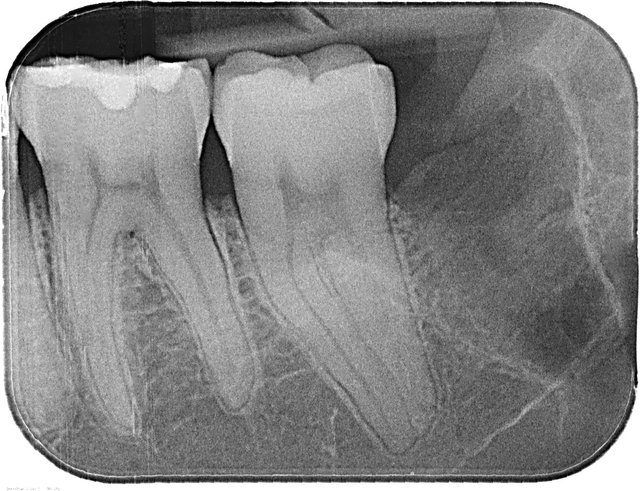

Tiefe Karies wegen eines benachbarten Weisheitszahnes

Tiefe Karies wegen eines benachbarten Weisheitszahnes ...